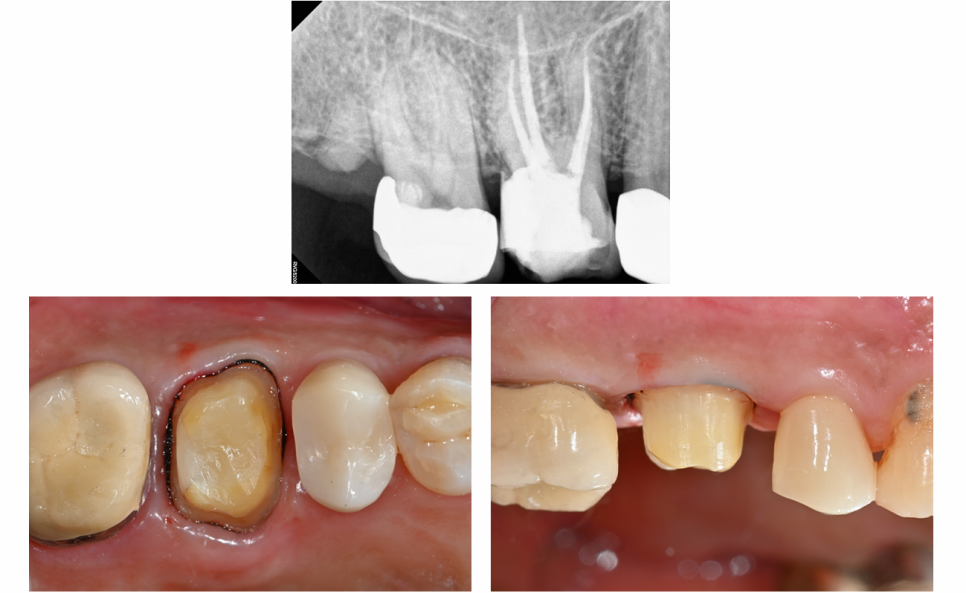

충치를 제거 했지만 잇몸아래까지 손상, 금이 가 있는 치아

기존 inlay를 제거했는데.....

x-ray에 보였던 것보다는 훨씬 더 상태가 좋지 않았고,

2차 충치들을 제거하고 보니

이번에는 잇몸 아래까지 치아가 많이 손상되어 있음을 확인했습니다

금도 꽤 깊이까지 진행되어 있었구요😭

상태가 좋지 않지만.....

포기하지 않았습니다

그래도 살려야지요!🙏

이미 신경이 죽어있는 상태라 신경치료를 먼저 진행했습니다

예스미르치과에서는

보존과 전문의 원장님이

직접 현미경으로 신경치료를 진행합니다

오래가는 크라운 치료를 위해 보철과 원장님께서 치아를 다듬은 모습!

신경치료를 잘 마무리 하고

치아를 보호하기 위해

지르코니아 크라운으로 씌워드렸습니다